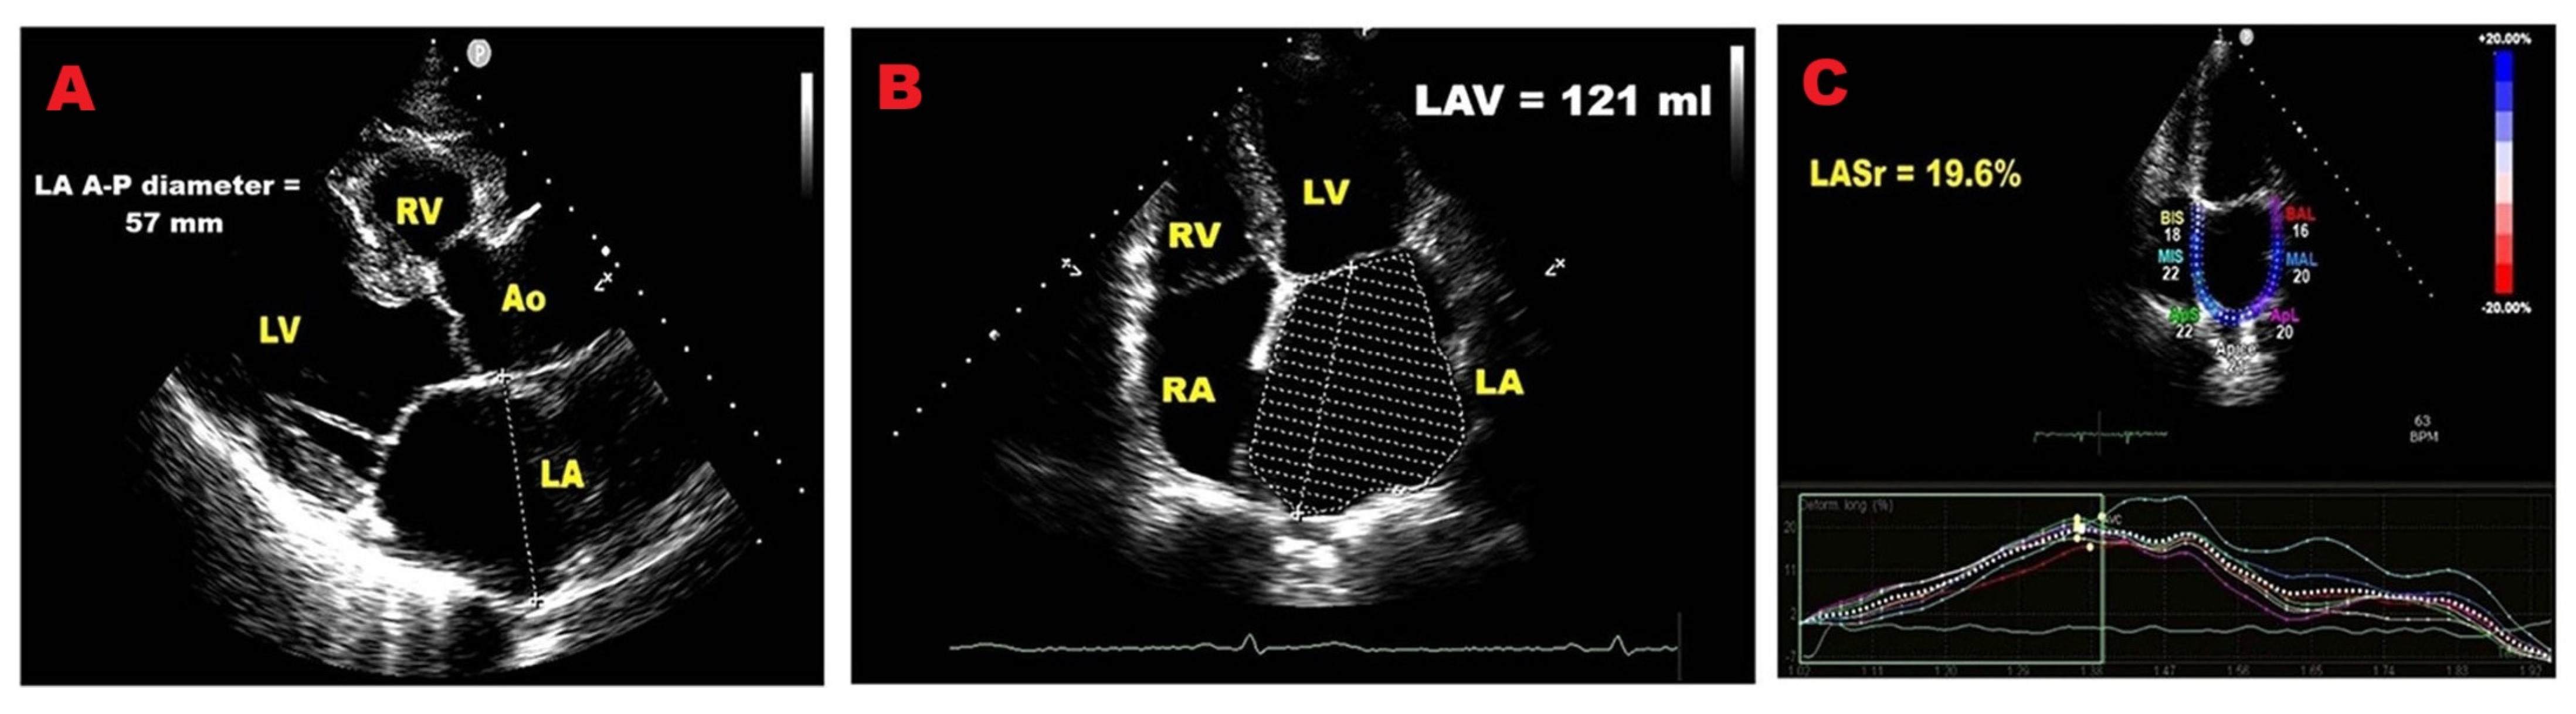

3.5. Left Atrial Size

3.6. Left Atrial Reservoir Strain